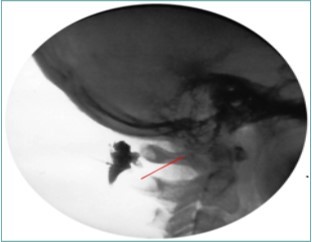

Because of the proximity to the vertebral artery and the potential risk of intravascular injection, few interventionalists have been interested in AA injections, and, since the proximal GON travels over the posterior arch of the atlas, even fewer have been interested in direct injections of the proximal GON. In an effort to avoid the “locked-in” syndrome complication seen with occipital injections, Dr. Gabor Racz developed a suboccipital approach to the suboccipital space in 1982, which has recently become more popular7, 8. A curved, bullet-tipped needle with side port injection, attached tubing, and wings (dubbed the “Stealth needle”™ because of its resemblance to the Stealth bomber) Figure 5 is used to approach the suboccipital triangle from above. Since the underlying pathology is usually bilateral, the procedure is usually performed bilaterally.The patient is positioned prone on the fluoroscopy table, with the neck in flexion; the hair is pulled cephalad, and the suboccipital area is sterilely prepped and draped. The inion and conjoined tendon are identified by palpation and the nuchal line is identified by fluoroscopy; the entry site should be 2cm lateral to the midline on the nuchal ridge. After making sure by palpation that the planned entry is not directly over the occipital artery, a small skin wheal of local anesthetic is injected via a 30g needle. Because the galea is so strong, an 18g needle is used to create a small stab incision in the scalp and deep fascia to facilitate the entry of the blunt-tipped needle. Standing at the head of the bed, the Stealth needle is held by the wings like a butterfly IV needle, and, with tip facing down and toward the feet Figure 6 the needle is advanced caudally. The needle position is initially identified on an anterior-posterior fluoroscopy view, with the target medial to the superior pars of C2 Figure 7 The needle is advanced through the muscle and fascial layers of the trapezius and semispinatus with confirmation of location on lateral view, aiming for the superior lamina of C2 at the level of the spinous processes Figure 8. Contrast is injected to verify needle placement Figure 9 followed by 10 cc of local anesthetics and steroids (4.5ccs 0.2% ropivicaine, 4.5ccs 1% lidocaine, and 10mg of dexamethasone on each side) to perform an adhesiolysis, freeing up the greater occipital nerves Figure 10 Because this technique is usually performed bilaterally, lower concentrations of local anesthetic are used to avoid toxicity issues.

Figure 9.Lateral Fluoroscopic image showing initial contrast location deep to the suboccipital muscles; red line corresponds to the level of the inferior oblique capitus muscle. (Image courtesy of Gabor Racz, MD)

Lateral Fluoroscopic image showing initial contrast location deep to the suboccipital muscles; red line corresponds to the level of the inferior oblique capitus muscle. (Image courtesy of Gabor Racz, MD)